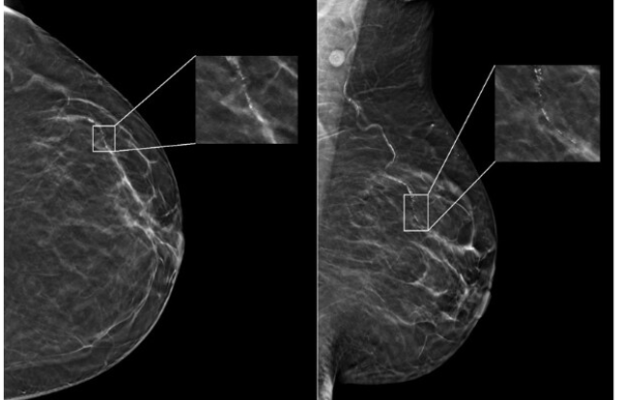

In a newly-published study of nearly 5,000 screening mammograms interpreted by an FDA-approved AI algorithm, patient characteristics such as race and age influenced false positive results. The study’s results, “Patient Characteristics Impact Performance of AI Algorithm in Interpreting Negative Screening Digital Breast Tomosynthesis Studies” were published today in the RSNA journal Radiology. Image courtesy: RSNA Radiology (Nguyen, DL and Ren, Y et al)

A commercially available AI algorithm interpreted each exam in the subset of mammograms, generating both a case score (or certainty of malignancy) and a risk score (or one-year subsequent malignancy risk).